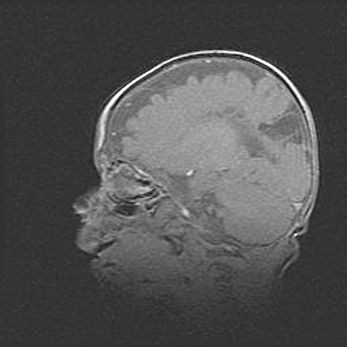

Открытая гидроцефалия.

Возраст: 9 месяцев 12 дней

Вес: 6800 г

Пол: мужской

Окружность головы: 41,5 см

Срок гестации: 28 недель

Гидроцефалия головного мозга у новорожденных имеет характерный признак: опережающий рост окружности головы приводит к визуально хорошо определяемой гидроцефальной форме сильно увеличенного в объёме черепа. Детские неврологи определяют следующие симптомы гидроцефалии у грудничков: выбухающий напряжённый родничок, частое запрокидывание головы, смещение глазных яблок к низу.